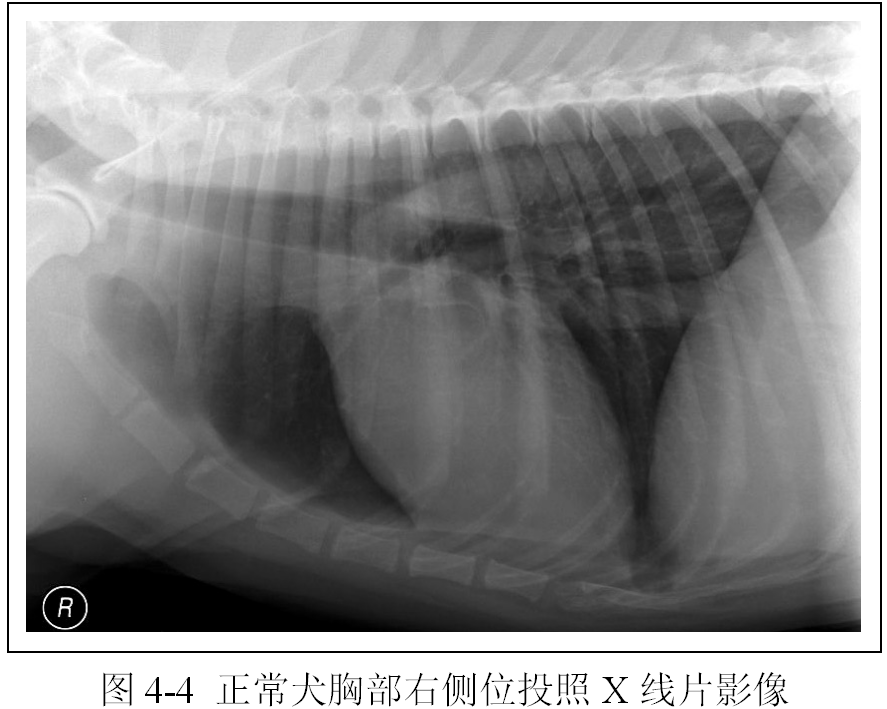

(2)识别胸椎、肋骨、胸骨、横膈外围结构影像(图4-4、4-5、4-6、4-7,注意观片灯评估X线影像时X线片的正确放置)。

(3)识别心脏、大血管、肺脏、气管、支气管影像(图4-4、4-5、4-6、4-7)。

(4)区分右侧位和左侧位以及腹背位和背腹位投照的明显区别(图4-4、4-5、4-6、4-7)。